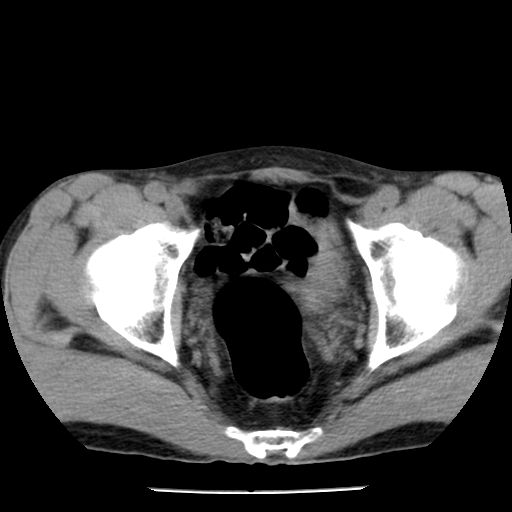

男,59岁,“结核性胸膜炎”30余年,胸部经常疼痛,多次x检查提示“肺部”炎症。腹部疼痛5日,b超提示:“肝内短管结石,余显示不清,建议进一步检查。”

两肺结核并右侧胸腔积液;脾脏、腹腔及腹膜后淋巴结结核[陈旧性];肝内胆管结石

胸部腹部都是结核(双肺。纵隔淋巴结,肝脏,脾脏,肠系膜)

两肺结核并右侧胸腔积液;脾脏、腹腔及腹膜后淋巴结结核[陈旧性];肝内胆管结石。直肠息肉?